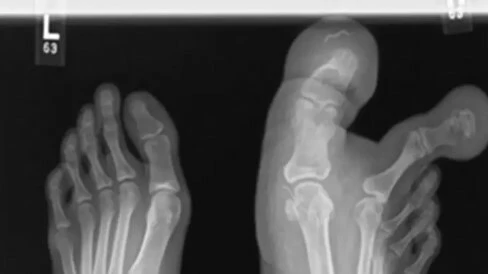

Yürüme zorluğu yaşayan kızın durumunu inceleyen sağlık ekipleri, "Düz radyografiler ve MRI bulguları, birinci ve ikinci ayak parmakları çevresinde, birinci metatarsın medial ve lateral yönlerinde, ayağın medial plantar kemerine kadar uzanan yağ dokusu birikimini ortaya çıkardı. MDL çok nadir görülen bir konjenital lokalize devlik hastalığıdır ve cerrahi konsültasyon sıklıkla kozmetik nedenlerden dolayı yapılmaktadır" ifadelerini kullandı.